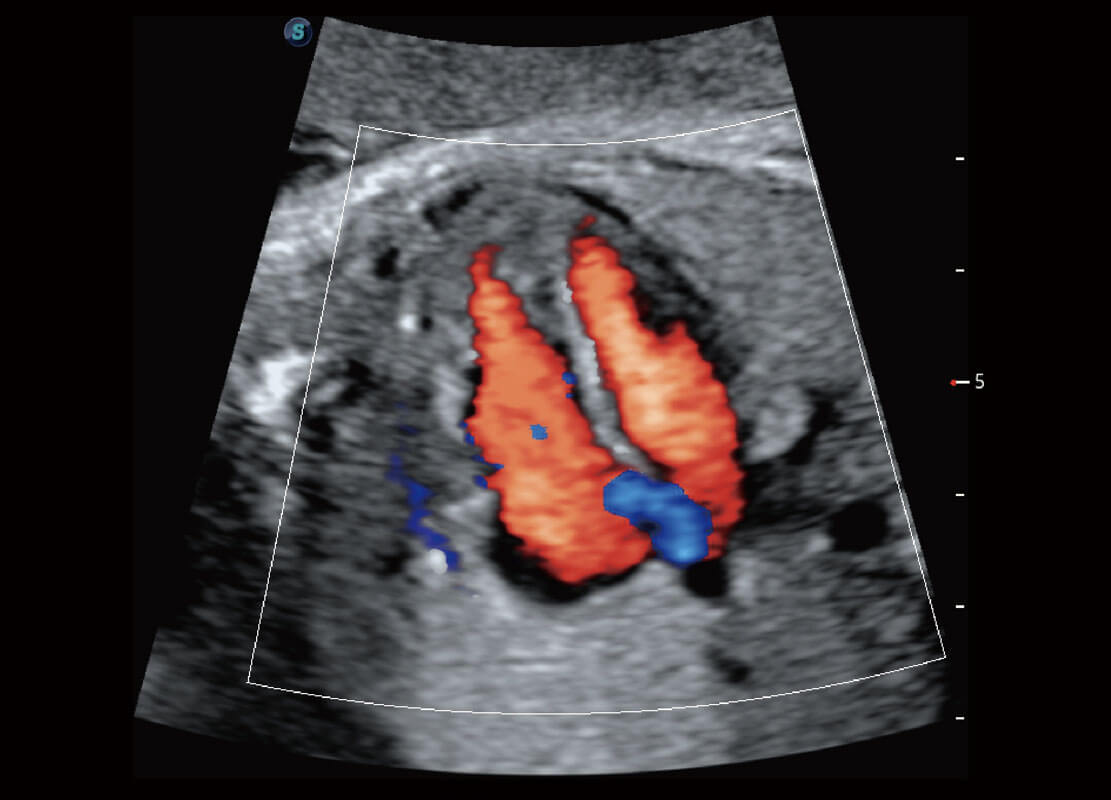

P60優(yōu)異的圖像質(zhì)量搭載專科探頭,在婦科基礎(chǔ)疾病的診斷、卵泡生長(zhǎng)的監(jiān)測(cè)、輸卵管通暢情況的判別等方面為您提供生殖應(yīng)用方案。

腔內(nèi)婦科-宮腔分離